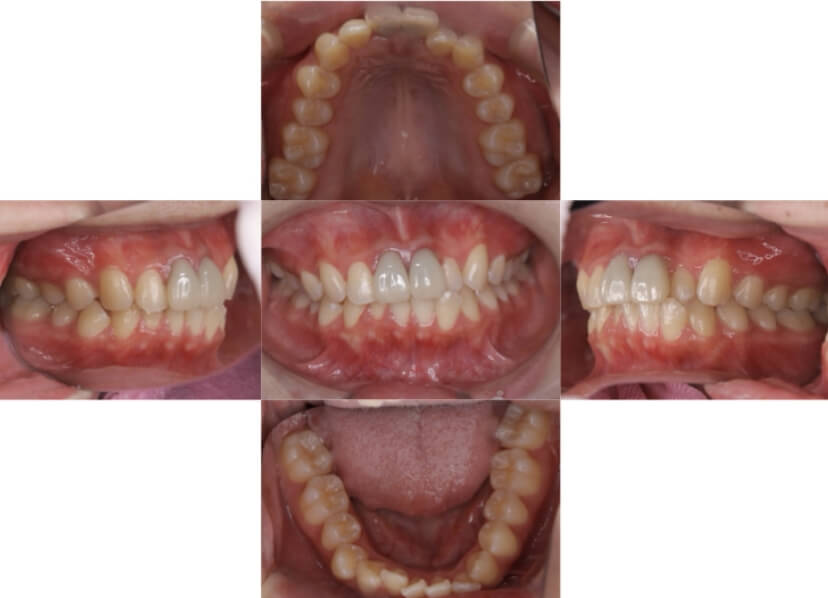

症例4

下顎前突、叢生

抜歯

ブラケット矯正

上下顎叢生、反対咬合(上下の前歯のガタガタ、若干受け口)のケースです。

装置はラビアル(上下表側)で、上下顎の小臼歯を4本抜歯を行っています。抜歯したスペースを使って、上下の叢生改善と前歯の受け口の改善を行っています。

主訴 前歯のガタガタを治したい。

年齢・性別 45歳 女性

お住まいの地域 神奈川県川崎市

治療方針 抜歯スペースを利用して上前歯の叢生(ガタガタ)の改善と受け口の改善

抜歯部位 上顎左右第一小臼歯、下顎左右第二小臼歯

使用装置 ラビアル(上下表側)、顎間ゴム

治療期間 2年6か月

治療回数 20回

リテーナー クリアリテーナー

BEFORE

AFTER